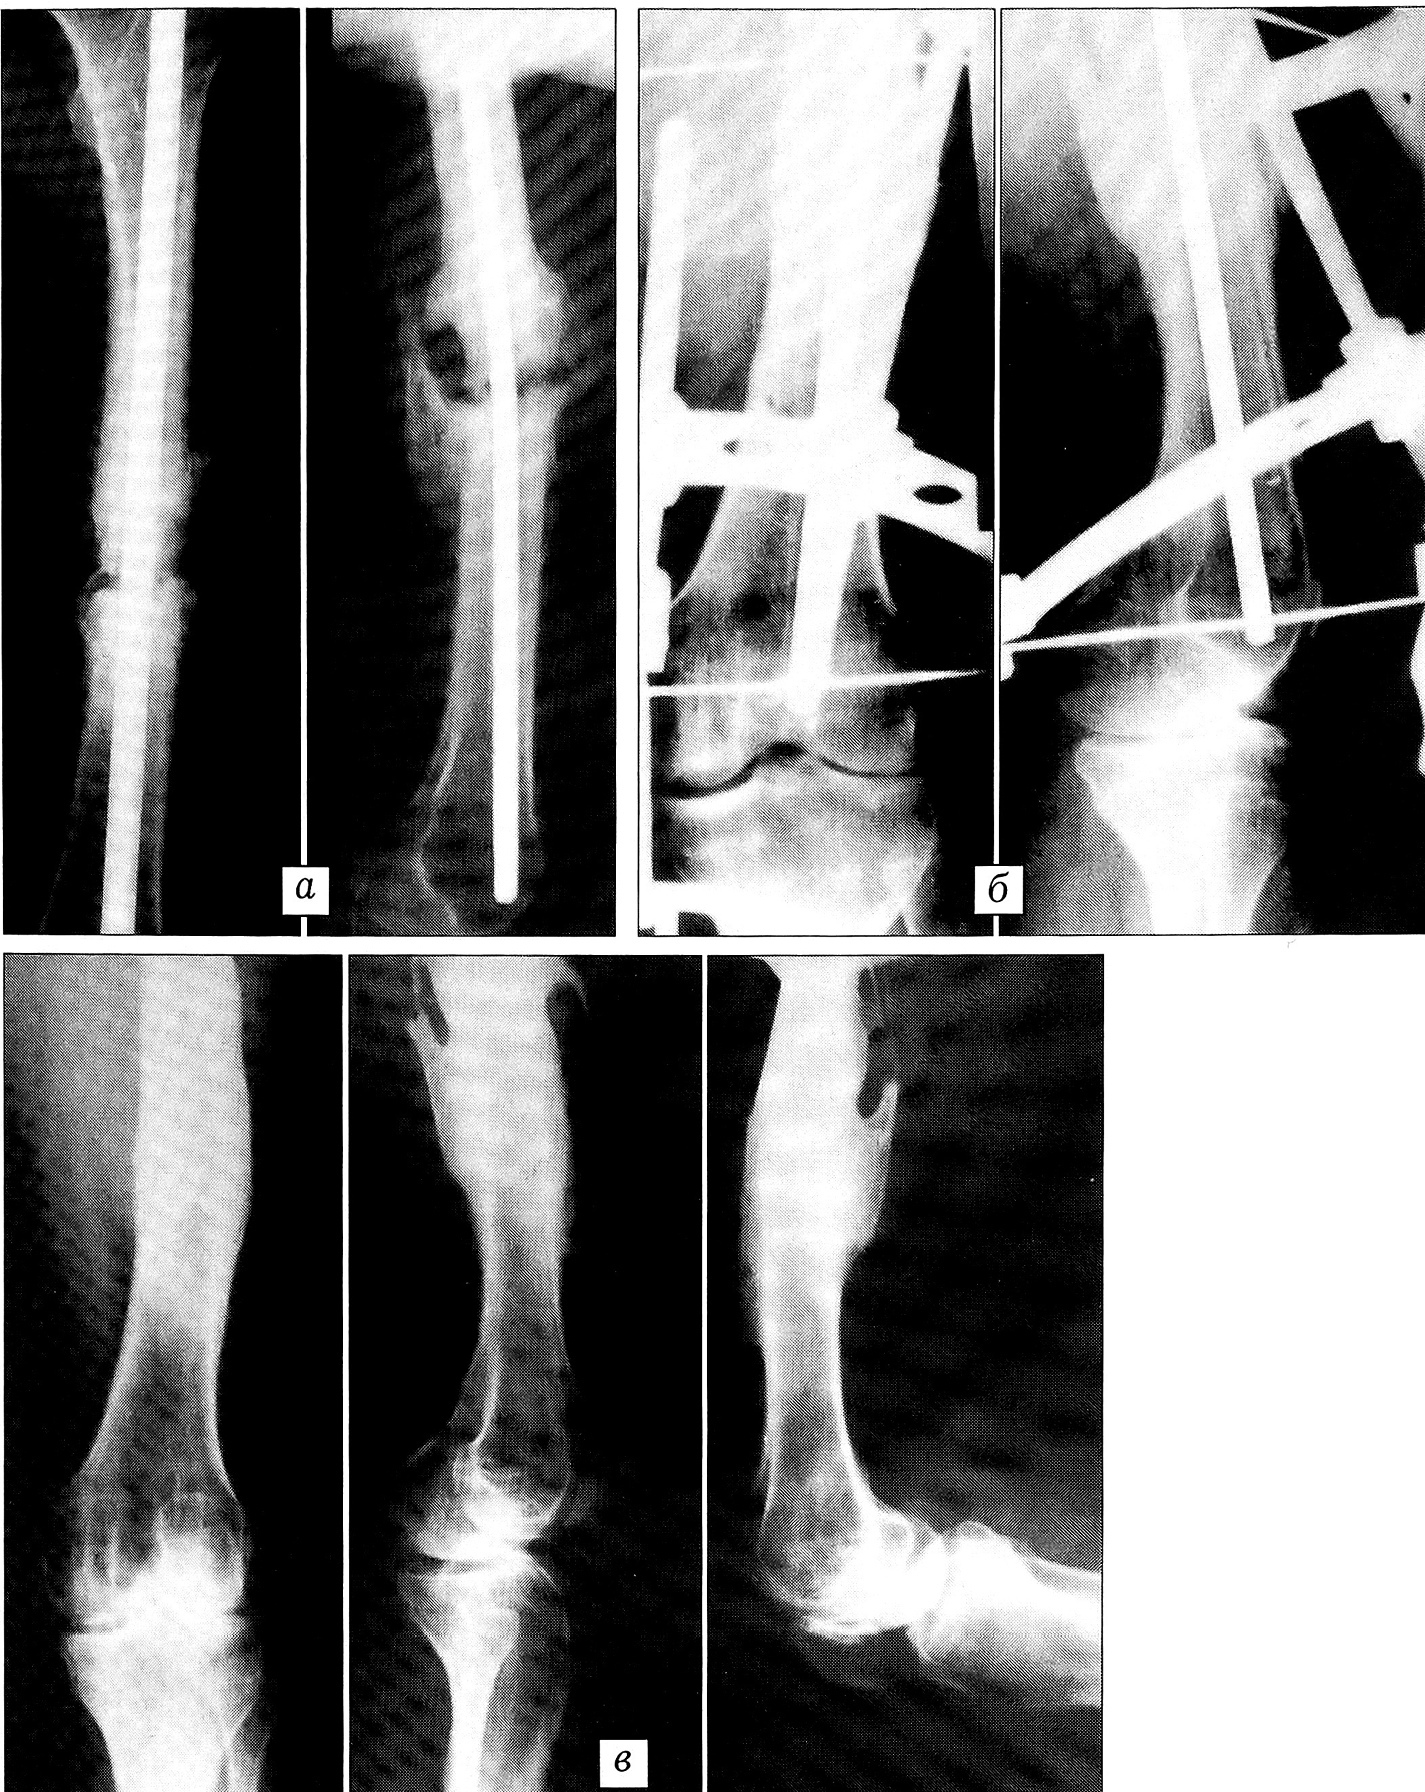

Пример 7. Больной П ., 29 лет, поступил в ЦИТО по поводу застарелых двойных переломов лучевой и локтевой костей (рис. 7, а). По месту жительства пациенту через 2 нед после травмы был произведен интрамедуллярный остеосинтез обеих костей предплечья штифтами Богданова — переломы не срослись. Наложен облегченный аппарат чрескостной фиксации, состоящий из четырех спиц и скоб (рис. 7, б). Через 3 мес клинически и рентгенологически констатирована консолидация обоих переломов (рис. 7, в).

Рис. 7. Пример 7.Рентгенограммы больного П.a — двойные переломы лучевой и локтевой костей;б — несросшиеся переломы обеих костей после интрамедуллярного остеосинтеза. Наложен аппарат чрескостной фиксации;в — через 3 мес: переломы срослись, аппарат снят.